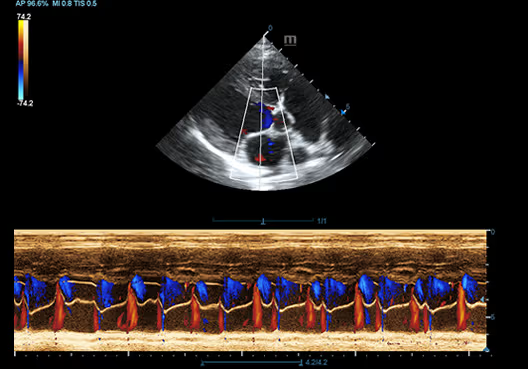

Kedi Mesanesi

Kedi Mesanesi